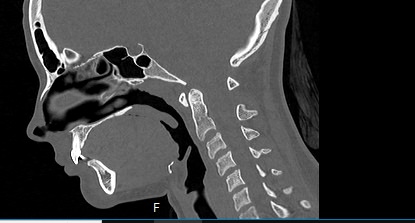

Мультиспиральная компьютерная томография челюстно-лицевой области относится к лучевым методам исследования и включает в себя сканирование верхней и нижней челюстей, зубов, височно-нижнечелюстных суставов, мягкотканных структур ротовой полости. Преимуществами КТ является быстрота, безболезненность и неинвазивность (то есть исследование не требует вмешательства в организм).

В результате сканирования получается серия изображений, которые отображают состояние челюстно-лицевой зоны, особенности анатомического строения и позволяют выявить воспалительные изменения, травматические повреждения, опухолевые образования, аномалии развития. Проявления артроза височно-нижнечелюстных суставов могут создавать неприятные ощущения при жевании. Также зачастую воспалительные изменения придаточных пазух носа связаны с пролабированием зубов верхней челюсти в область альвеолярных бухт верхнечелюстных синусов.

В наших медицинских центрах обследование челюстно-лицевой зоны проводится на современных мультиспиральных компьютерных томографах экспертного класса TOSHIBA AQUILION. 64- и 128-срезовый компьютерные томографы послойно сканируют исследуемую область с шагом от 0,5 мм, получая детальные изображения высокого уровня четкости и контрастности.

С помощью цифровой обработки данных проводится объемная реконструкция и построение 3D-изображений челюстно-лицевой области, что дает возможность визуализировать пространственное соотношение анатомических структур и повышает точность диагностики. При этом возможности аппаратов обеспечивают пониженный уровень дозы облучения для организма человека.